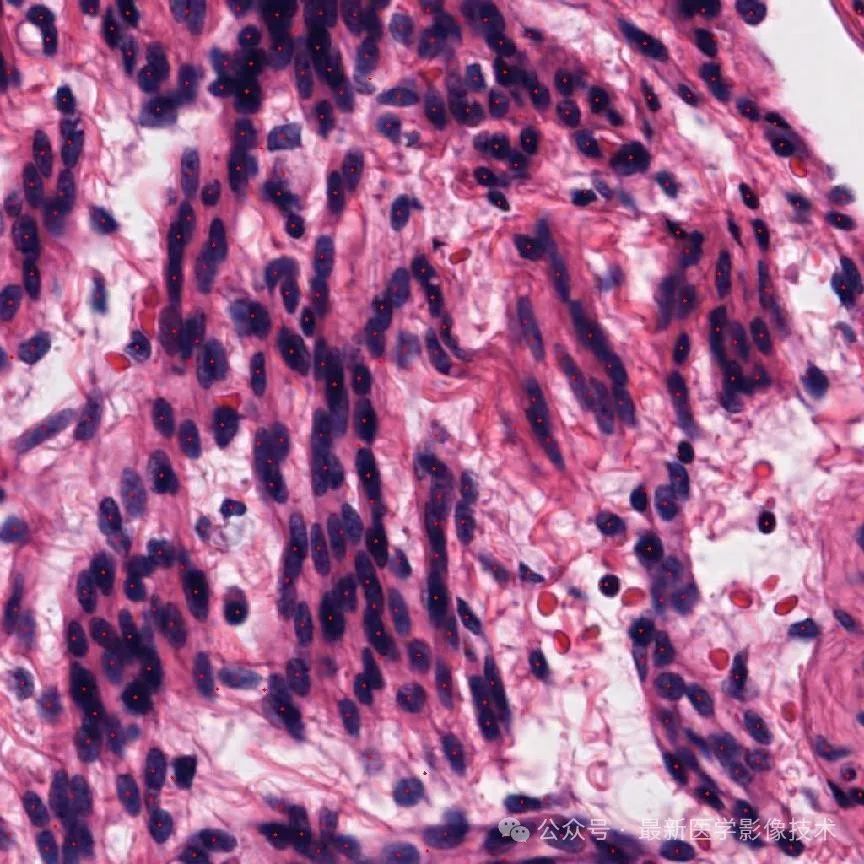

4、验证集部分检测结果

第一个是金标准结果,第二个是网络检测结果。

细胞检测结果